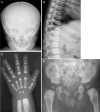

Methods and results: By whole exome sequencing in a boy with OSMD, we identified a homozygous 7 bp deletion (c.5938_5944delGAGTGGT) in the LRRK1 gene. His skeletal phenotype recapitulated that seen in the Lrrk1-deficient mouse. The shared skeletal hallmarks included severe sclerosis in the undermodelled metaphyses and epiphyseal margins of the tubular bones, costal ends, vertebral endplates and margins of the flat bones. The deletion is predicted to result in an elongated LRRK1 protein (p.E1980Afs*66) that lacks a part of its WD40 domains. In vitro functional studies using osteoclasts from Lrrk1-deficient mice showed that the deletion was a loss of function mutation. Genetic analysis of LRRK1 in two unrelated patients with OSMD suggested that OSMD is a genetically heterogeneous condition.